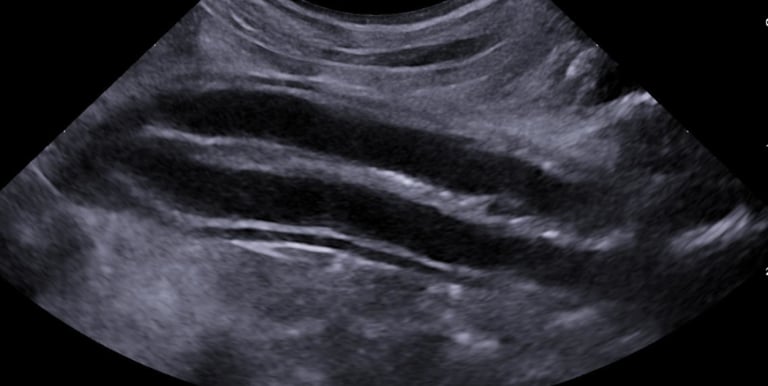

abdominal ultrasound

Complete abdominal ultrasound captures detailed videos and images of internal organs to aid in the diagnosis of various conditions and help guide treatment decisions.

Organs interrogated include liver, gallbladder, pancreas, adrenal glands, kidneys, bladder, spleen, colon, stomach, small intestines, lymph nodes, vessels, +/- reproductive organs.